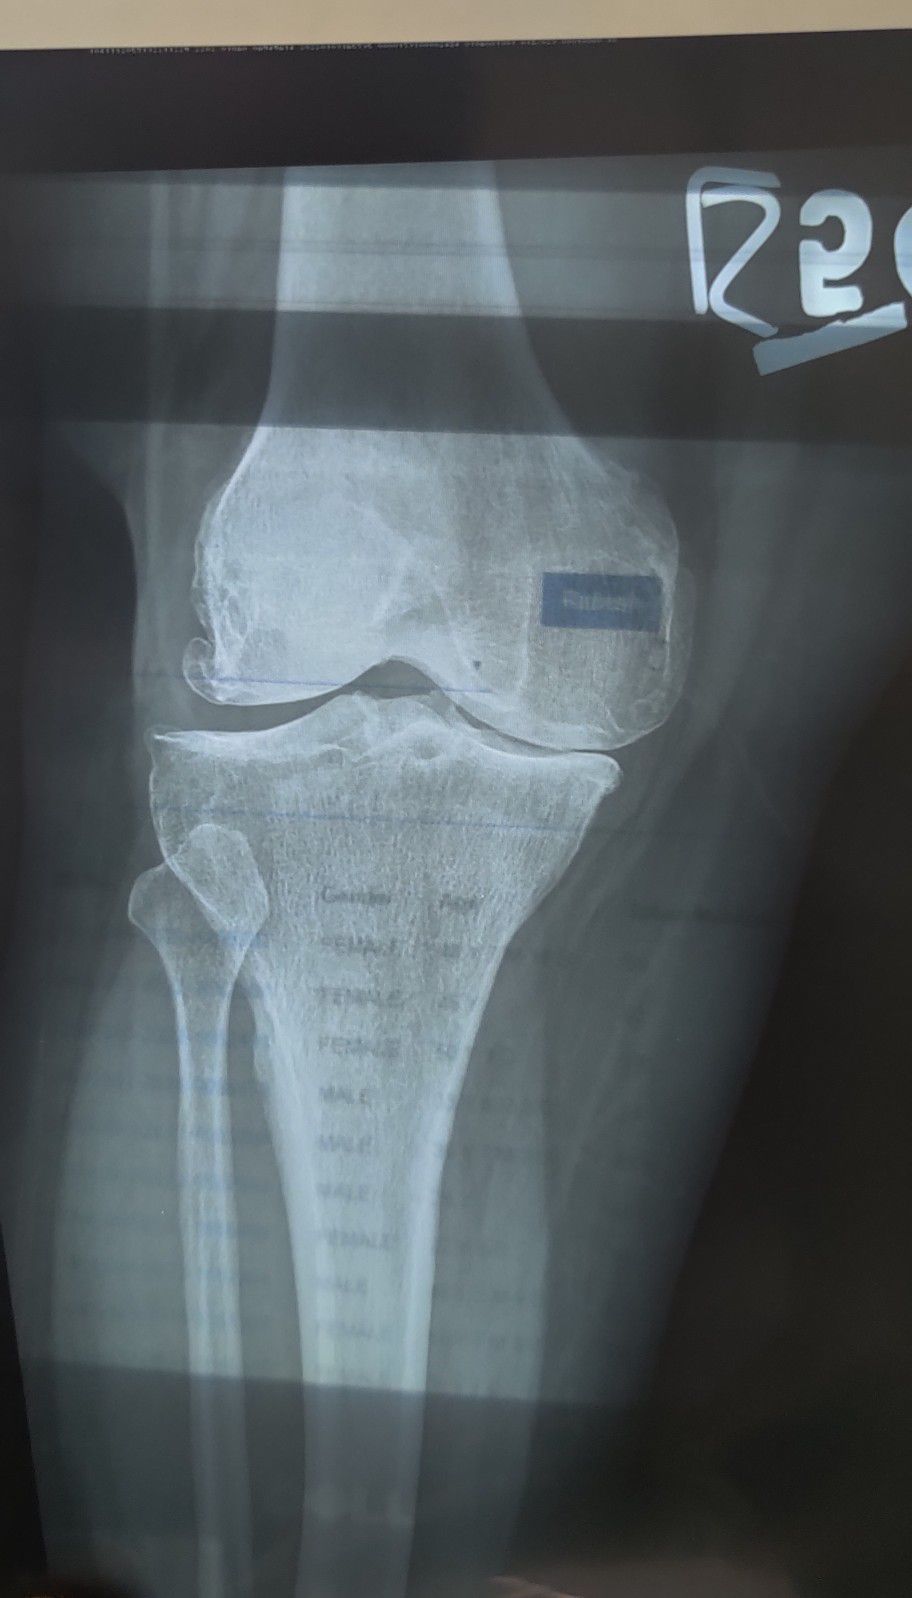

Osteoarthritis

Knee

Ortho